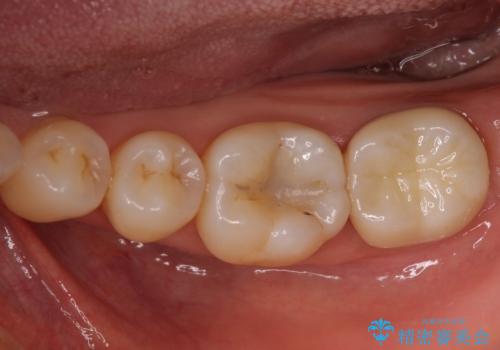

奥歯が痛い ゴールドクラウンによる補綴治療

- 近医にてむし歯治療を受けたところ、激痛が続き神経を除く必要があると診断され、当院を受診された患者様です。

診断の結果、神経を取り除く必要があったため、根管治療を行うこととしました。

咬み合わせの力が強いことや、極力歯の切削量を少なくしたいとのことで、ゴールドクラウン(PGAクラウン)にて補綴することとしました。

根管治療後は速やかに痛みが引き、不自由なく食事ができるようになりました。

上の奥歯であることから、審美性よりも機能性を優先され、ゴールドクラウンを選択されました。

装着後の違和感など一切なく、見た目もほとんど気にならないとのことで、患者様には大変満足していただけました。